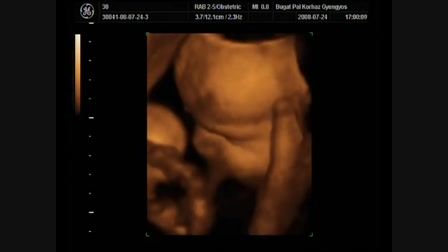

Levente 30 perces

Date: 2009. 09. 14.